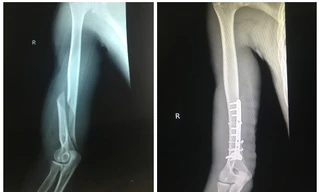

Sau khi đọ sức cùng bạn thông qua trò vật tay, nam thanh nhiên ở Quảng Yên, Quảng Ninh phải vào viện cấp cứu. Xương cánh tay bị gãy vặn xoắn một đoạn khoảng 8cm.